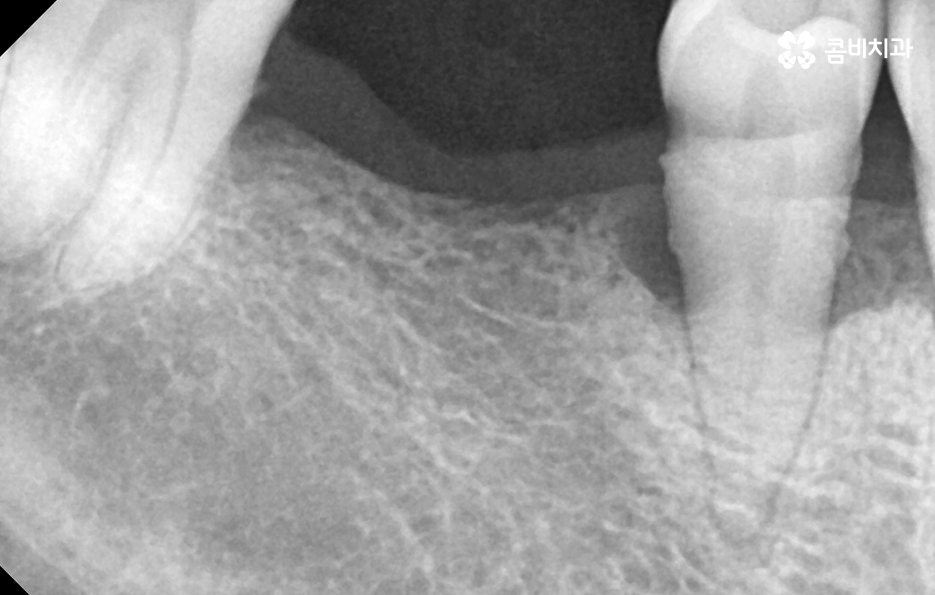

위 케이스의 노인임플란트 치료의 경우 치아의 균열부터 뿌리까지 깊어진 충치, 치주염 까지 복합적인 이유로 치아를 상실하고 여러 개의 임플란트를 식립한 사례라고 할 수 있는데요. 그래도 아직은 잔존하고 있는 치아가 많기 때문에 이미 상실한 치아에는 노인임플란트 각 위치에 맞게 적절한 치료를 받고 나머지의 자연치아에 대해서는 잘 관리하는 것이 중요한 시점이라 할 수 있어요

위 환자분의 케이스는 대부분 어금니 위주로 상실하여 노인임플란트 적절하게 식립하여 어금니의 저작기능을 수복했는데요. 노인임플란트 하면 건강보험에 대한 적용이나 저렴한 치료 비용에 대한 관심을 갖는 경우가 많긴 하지만 연령대에 따라 치아의 잔존율이 크게 급감하는 원인에 대해 잘 알아두시고 이제 치아를 하나 둘씩 잃기 시작했다면 이 시기부터 보다 적극적으로 자연치아를 보존하는 방법을 잘 숙지하시고 특히 주기적으로 치과 검진과 스케일링을 생활화 하는 것이 강조되고 있어요